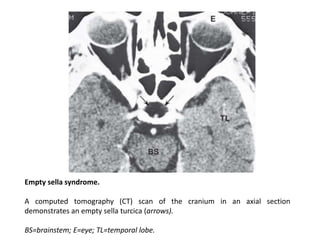

Empty sella syndrome.

A computed tomography (CT) scan of the cranium in an axial section

demonstrates an empty sella turcica (arrows).

BS=brainstem; E=eye; TL=temporal lobe.

Empty sella syndrome. Acomputed tomography (CT) scan of the cranium in an axial section demonstrates an empty sella turcica (arrows). BS=brainstem; E=eye; TL=temporal lobe.